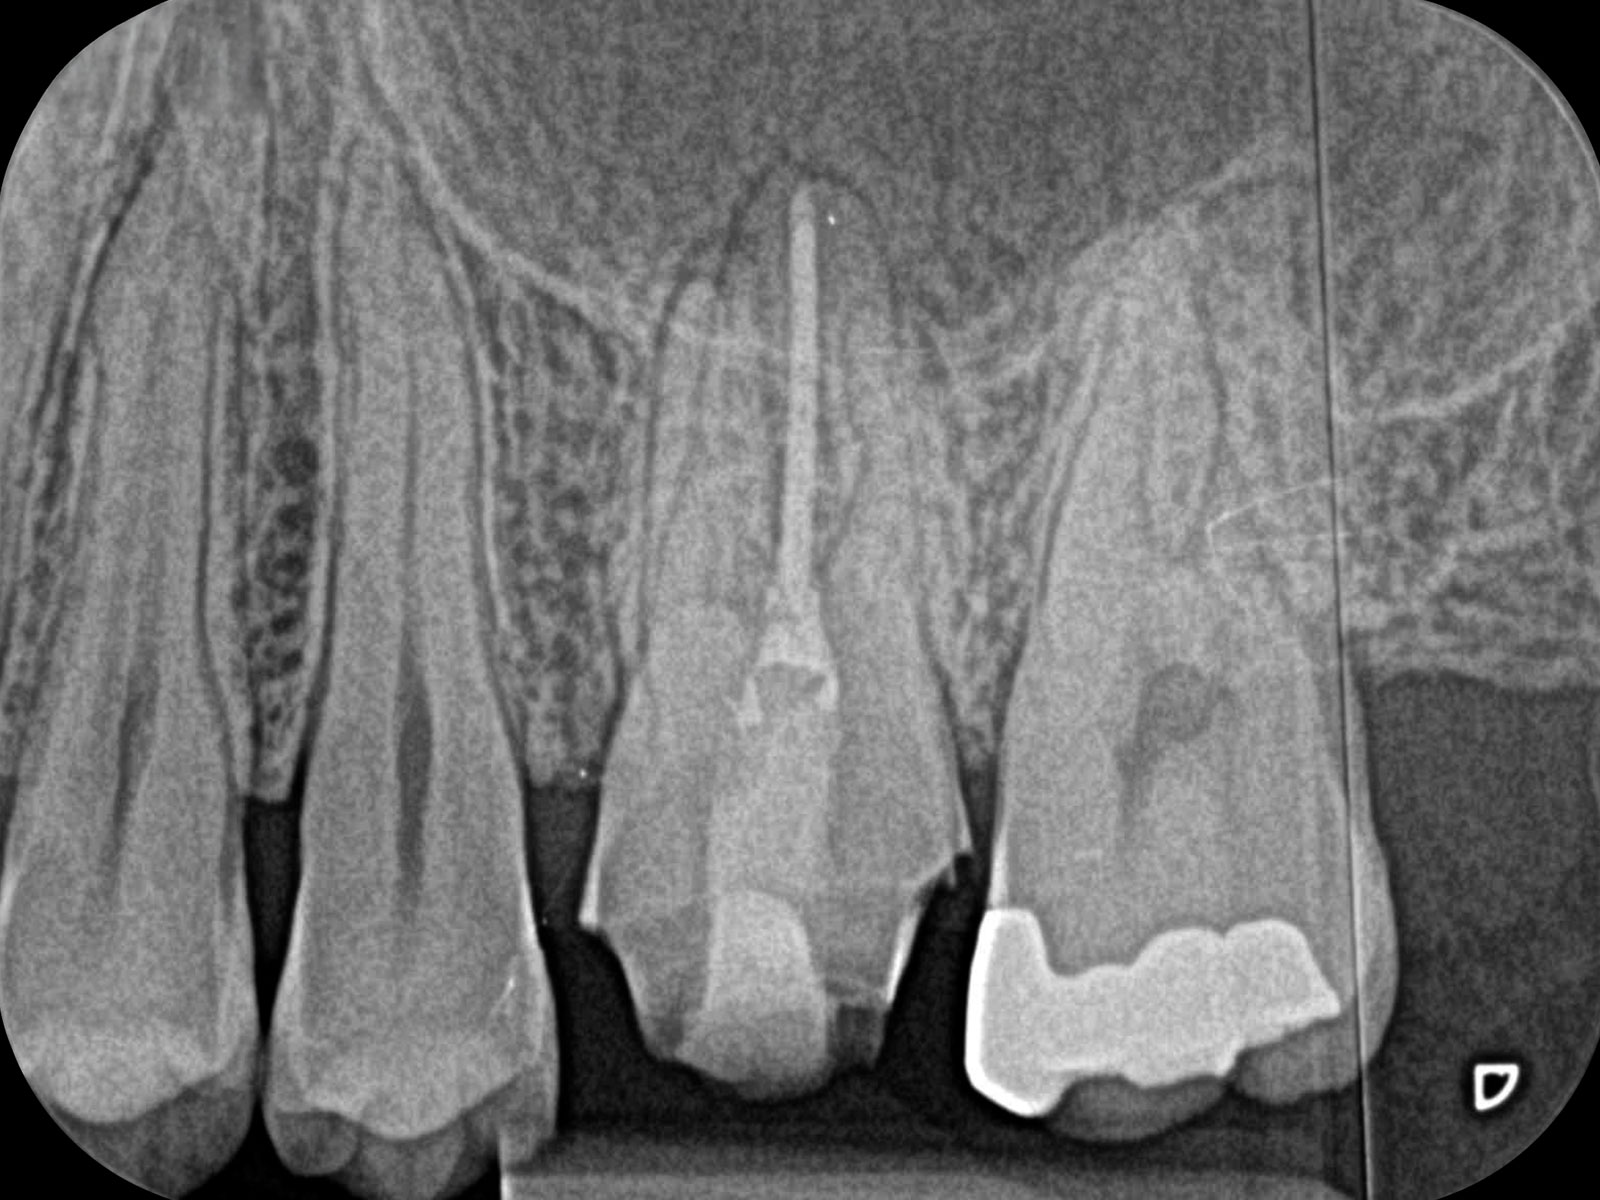

主訴: 噛むと痛い、左で食べれない。他の病院で神経が見つからない。根の先に病気がある。

通常だと手立てがなく、抜歯しかない歯も外科(根尖切除術)で治すことができます。